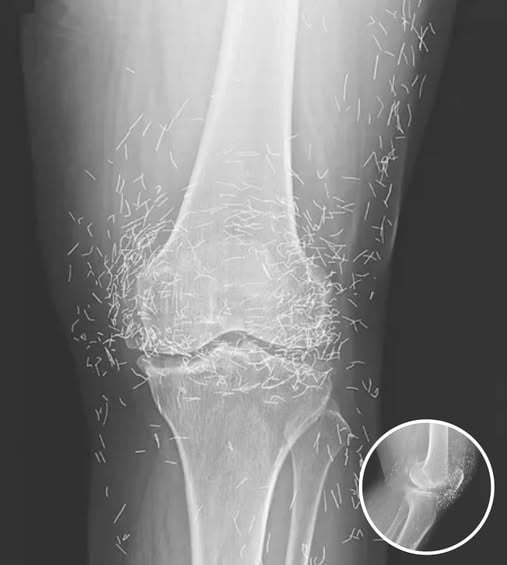

Doctors Stunned After Looking At This X-Ray Of Woman Suffering Joint Pain

A routine X-ray revealed an unexpected surprise when doctors examined the knees of a 65-year-old woman suffering from severe joint pain. What they found was nothing short of astonishing — hundreds of tiny gold needles embedded deep in her tissue. The woman, from South Korea, had been battling osteoarthritis for years. The painful condition breaks…